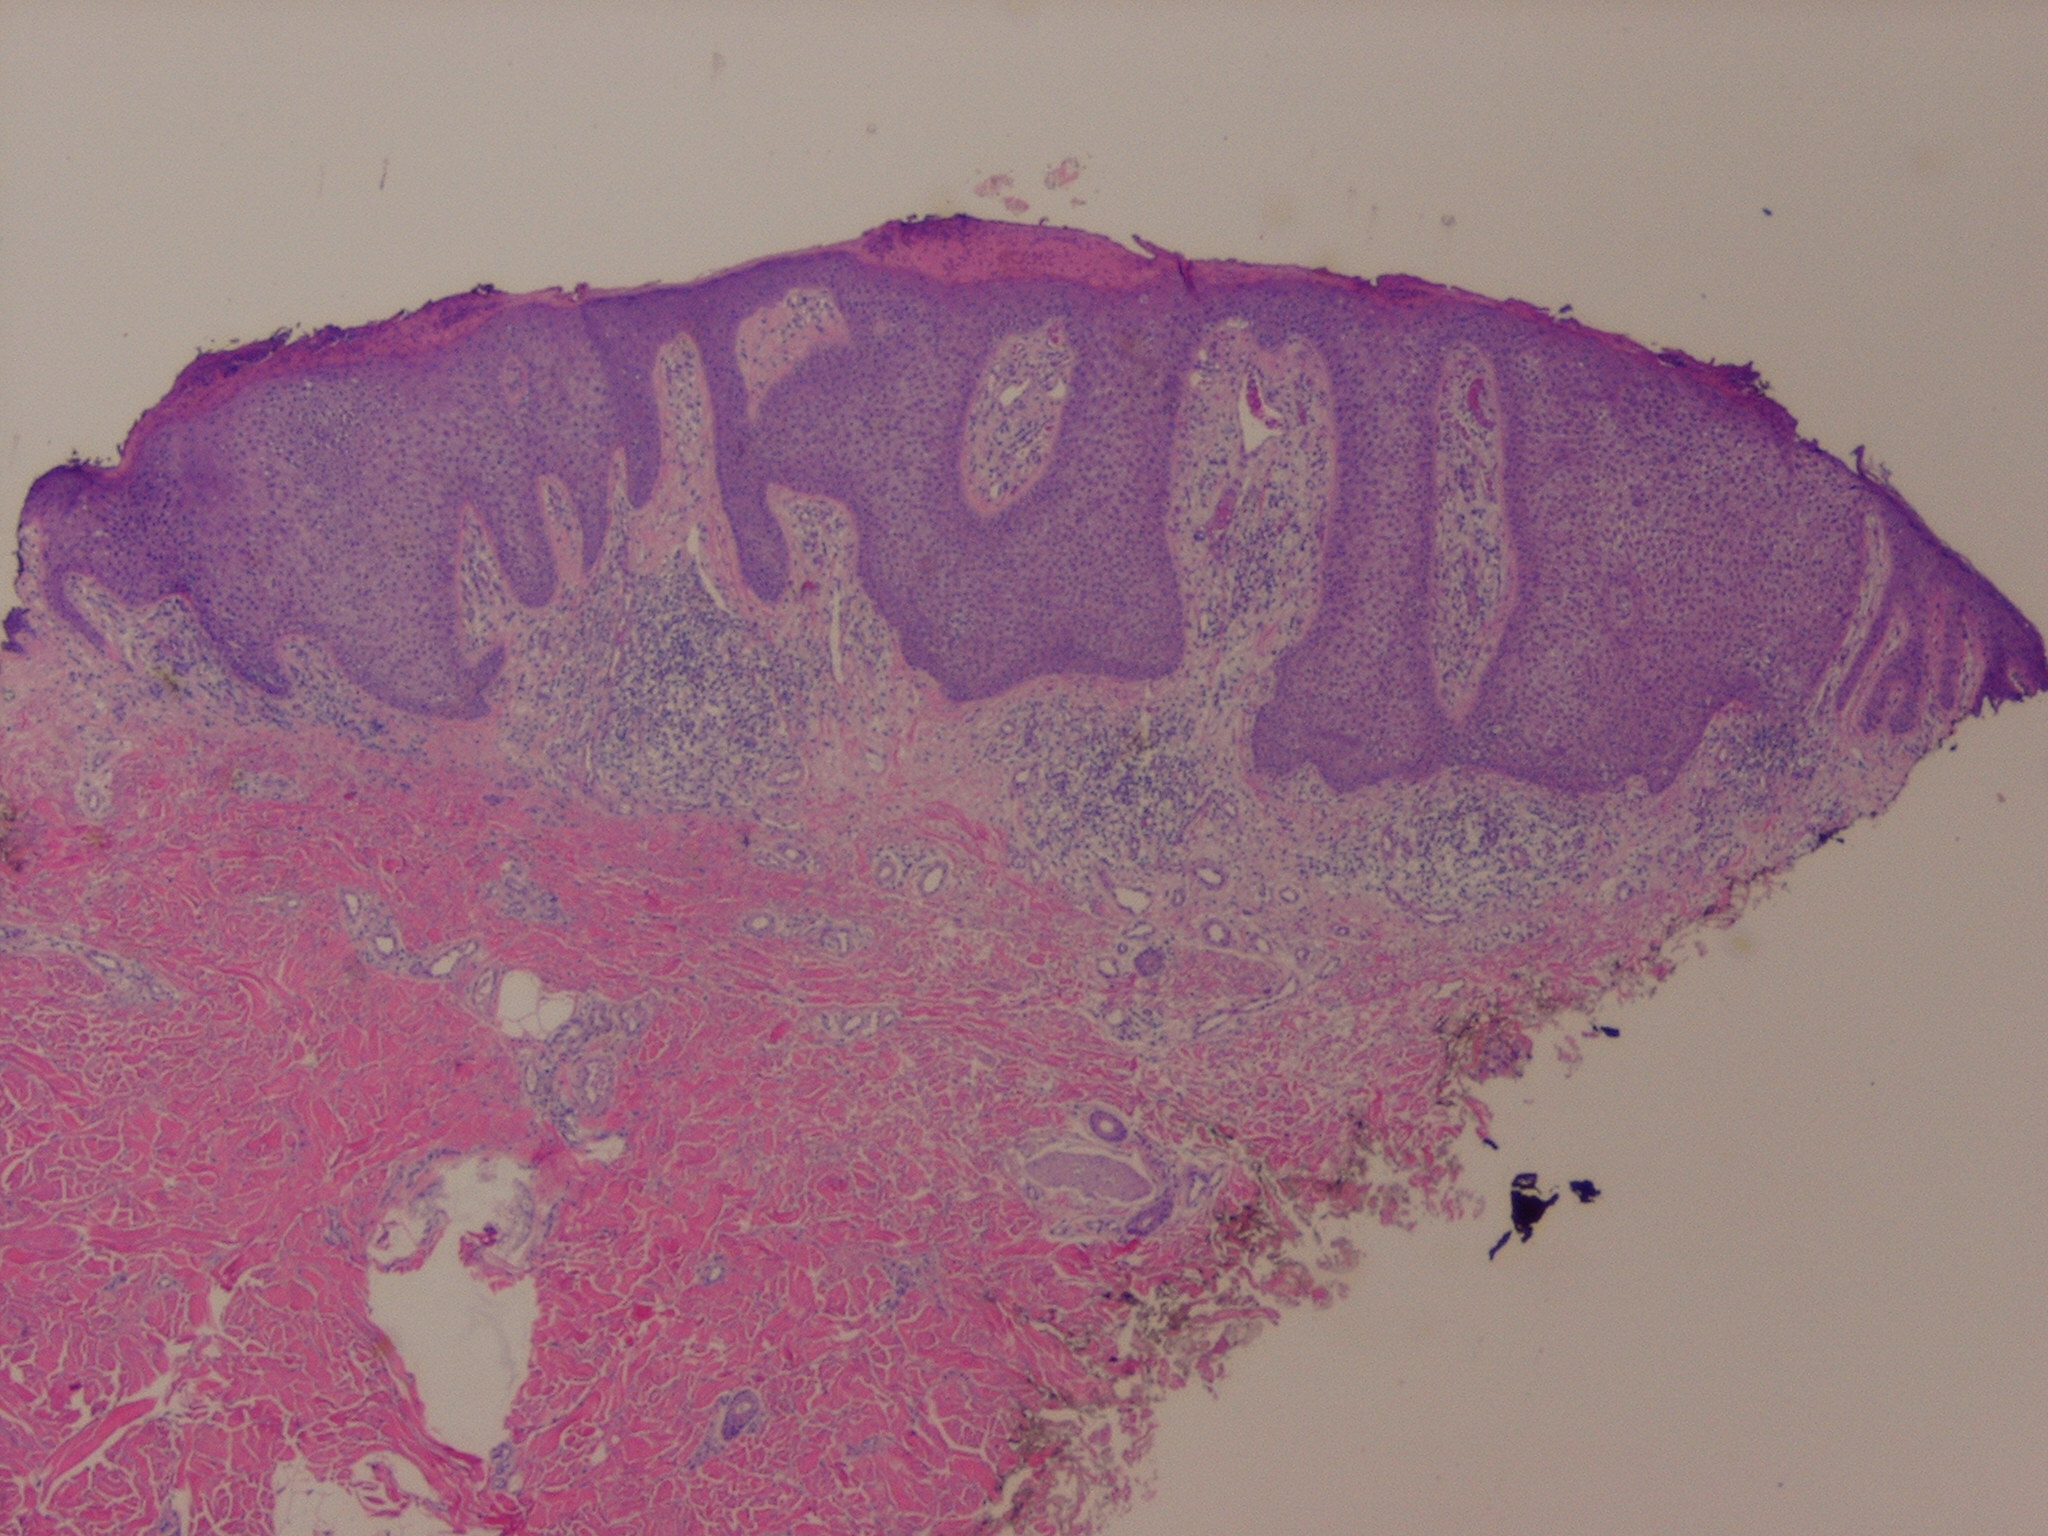

Within a sharply demarcated area of the epidermis

of cells of the basal cell layer, appear strikingly clear and slightly enlarged . The nuclei of the clear epidermal cells appear normal. When staining is carried out with the periodic acid-Schiff (PAS) reaction, the presence of large amounts of glycogen is revealed within the cells .

Slight spongiosis is present between the clear cells. The rete ridges are elongated and may show intertwining . The surface shows parakeratosis with few or no granular cells. The acrosyringia and acrotrichia within the tumor retain their normal stainability . There is an absence of melanin within the tumor cells, but dendritic melanocytes containing melanin are occasionally seen interspersed between the clear cells .

A conspicuous feature in most lesions is the presence throughout the epidermis of numerous neutrophils, many of which show fragmentation of their nuclei . The neutrophils often form microabscesses in the parakeratotic horny layer . Dilated capillaries are seen in the elongated papillae and often also in the dermis underlying the tumor In addition, a mild to moderately severe cellular infiltrate composed largely of lymphoid cells is present in the dermis. Some clear cell acanthomas appear papillomatous, so that they have the configuration of a seborrheic keratosis .

Beneath the tumor, some cases have shown hyperplasia of sweat ducts  or syringoma-like proliferations .